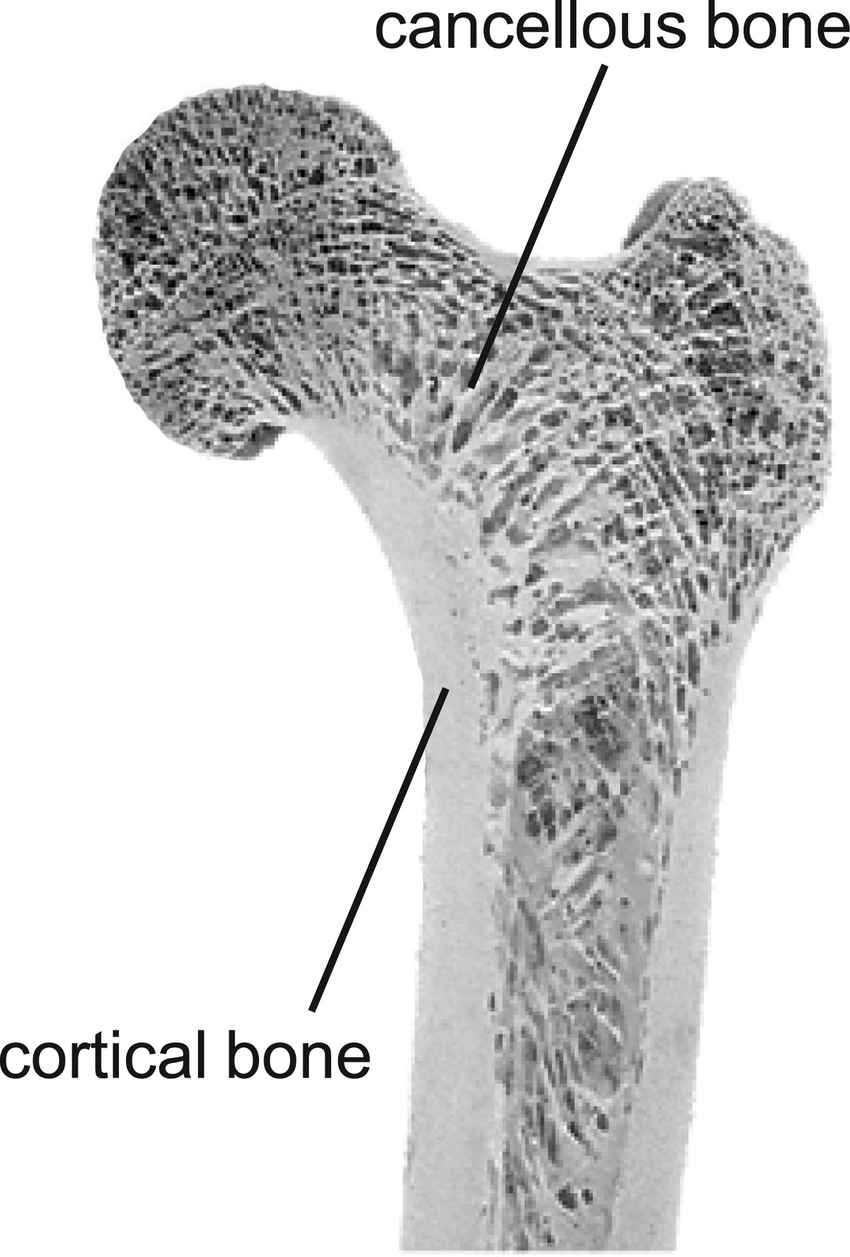

cortical (compact) bone is (inner//outer)

outer

cancellous (trabecular, spongy) bone is (inner//outer)

inner

(cancellous//cortical) bone has a trabeculae oriented lattice pattern

cancellous

what percent porosity is the density of cortical bone?

5-30% porous

what percent porosity is the density of trabecular bone?

30-90% porous